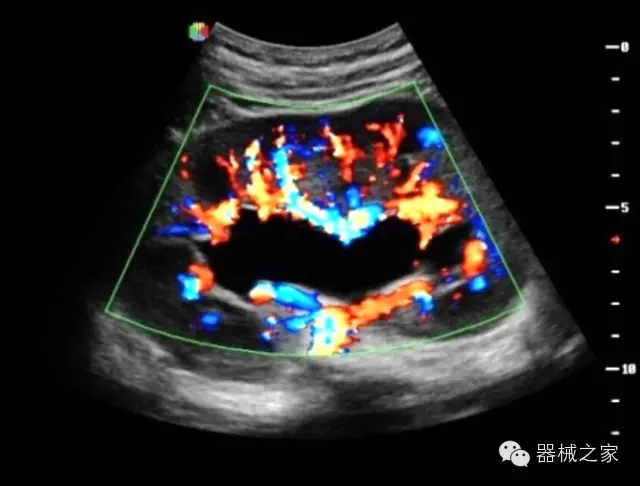

臨床圖片賞析

·獨有的HoloTM PW 實時3取樣門PW成像技術(shù),精確進(jìn)行血管診斷;

·一鍵優(yōu)化B、Color、PW,Auto Doppler自動識別血管位置、偏轉(zhuǎn)角度等,提高工作效率;

·30°超廣角精細(xì)偏轉(zhuǎn)成像技術(shù),更優(yōu)異的頻譜圖像;